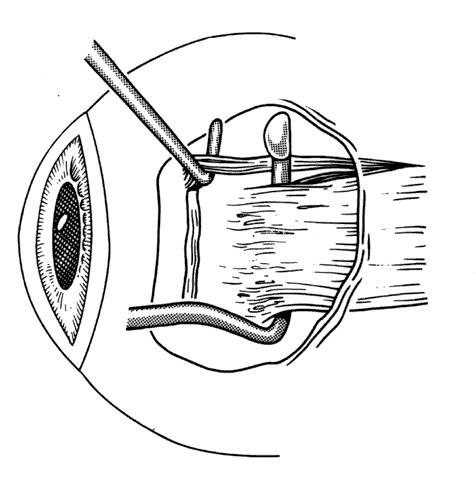

To detect and disrupt adhesions between the underside of the rectus muscle and the globe, or attachments between the lateral rectus and the inferior oblique muscle, a Jameson muscle hook is slid posteriorly.37 If an adhesion is encountered, it can usually be broken by gently disrupting the adhesion with a second Jameson hook (Figs. 23 and 24). If additional adherent tissue remains near the insertion, it should be removed prior to placement of sutures at the insertion of the tendon (Fig. 25).

Fig. 23. A Jameson muscle hook is placed under the insertion.

Fig. 24. Adhesions between the underside of the muscle and the sclera can be broken by gently passing the Jameson hook posteriorly. Failure to free up these adhesions will reduce or eliminate the effect of recession of the muscle.